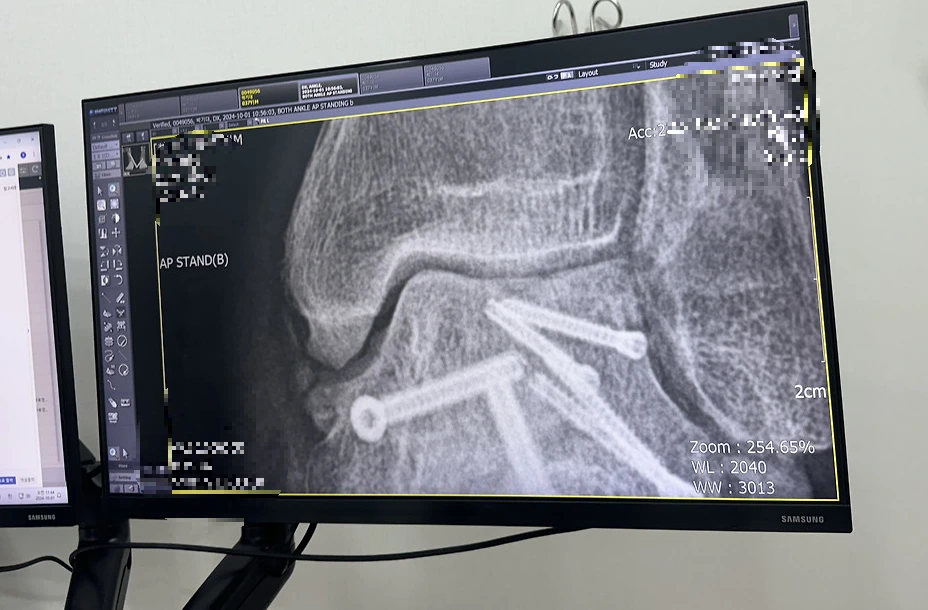

아침에 일어나면 발목은 더욱 굳어 있었다. 자는 동안 움직이지 않았기 때문이다. 발목이 굳는 현상은 20~30분 정도 그냥 않아 있어도 나타났다. 움직이지 않고 있으면 굳는 것이었다. 특히 발목이 굳을 때 45도로 굳기 때문에 발로 지면을 수직으로 디딜 수 없어 절뚝거릴 수밖에 없었다. 굳은 상태에서 계속 걸으면 굳은 상태가 풀어서 똑바로 걷기는 했지만 시간이 좀 걸렸다. 발목에 핀이 6개나 박혀있어서 그런지 이물감도 있었다. 부종은 덤이었다.

거골과 정강이 뼈사이 앞쪽 뼈가 자라 있다.

발목 상태는 확실히 예전보다 많이 좋아지고 있었다. 하지만 원래 상태로 돌아가기는 힘들 것 같다는 생각 때문에 좌절하기도 했다. 정기적으로 병원에 방문해 수술한 발목에 이상이 있는지 검사를 하였다. 병원에 방문할 때마다 x-ray와 CT 촬영을 했다. 어느 날 의사 선생님이 정강이 뼈과 거골사이에 뼈가 자랐다는 것을 발견하였다. 사고 날 때 정강이 뼈가 거골에 세게 부딪쳐 거골이 두 동강으로 분쇄 골절이 났다. 이 두동강으로 부러진 부분이 발목 앞쪽이고 이곳의 연골이 많이 손상되었다. 그리고 회복 중 그곳에 뾰족한 뼈가 자라났다. 의사 선생님은 자라난 뼈가 연골을 긁을 것을 걱정하셔서 발목을 앞으로 굽히지 말고 뒤쪽으로만 굽히는 연습을 하라고 하셨다. 그리고 뛰지 말고 자전거만 타라고 하셨다. 회복이 잘되고 있는 줄 알았는데 뜻밖의 상황이 벌어졌다. 평생 못 뛸 수도 있다는 생각에 걱정이 많아졌다.